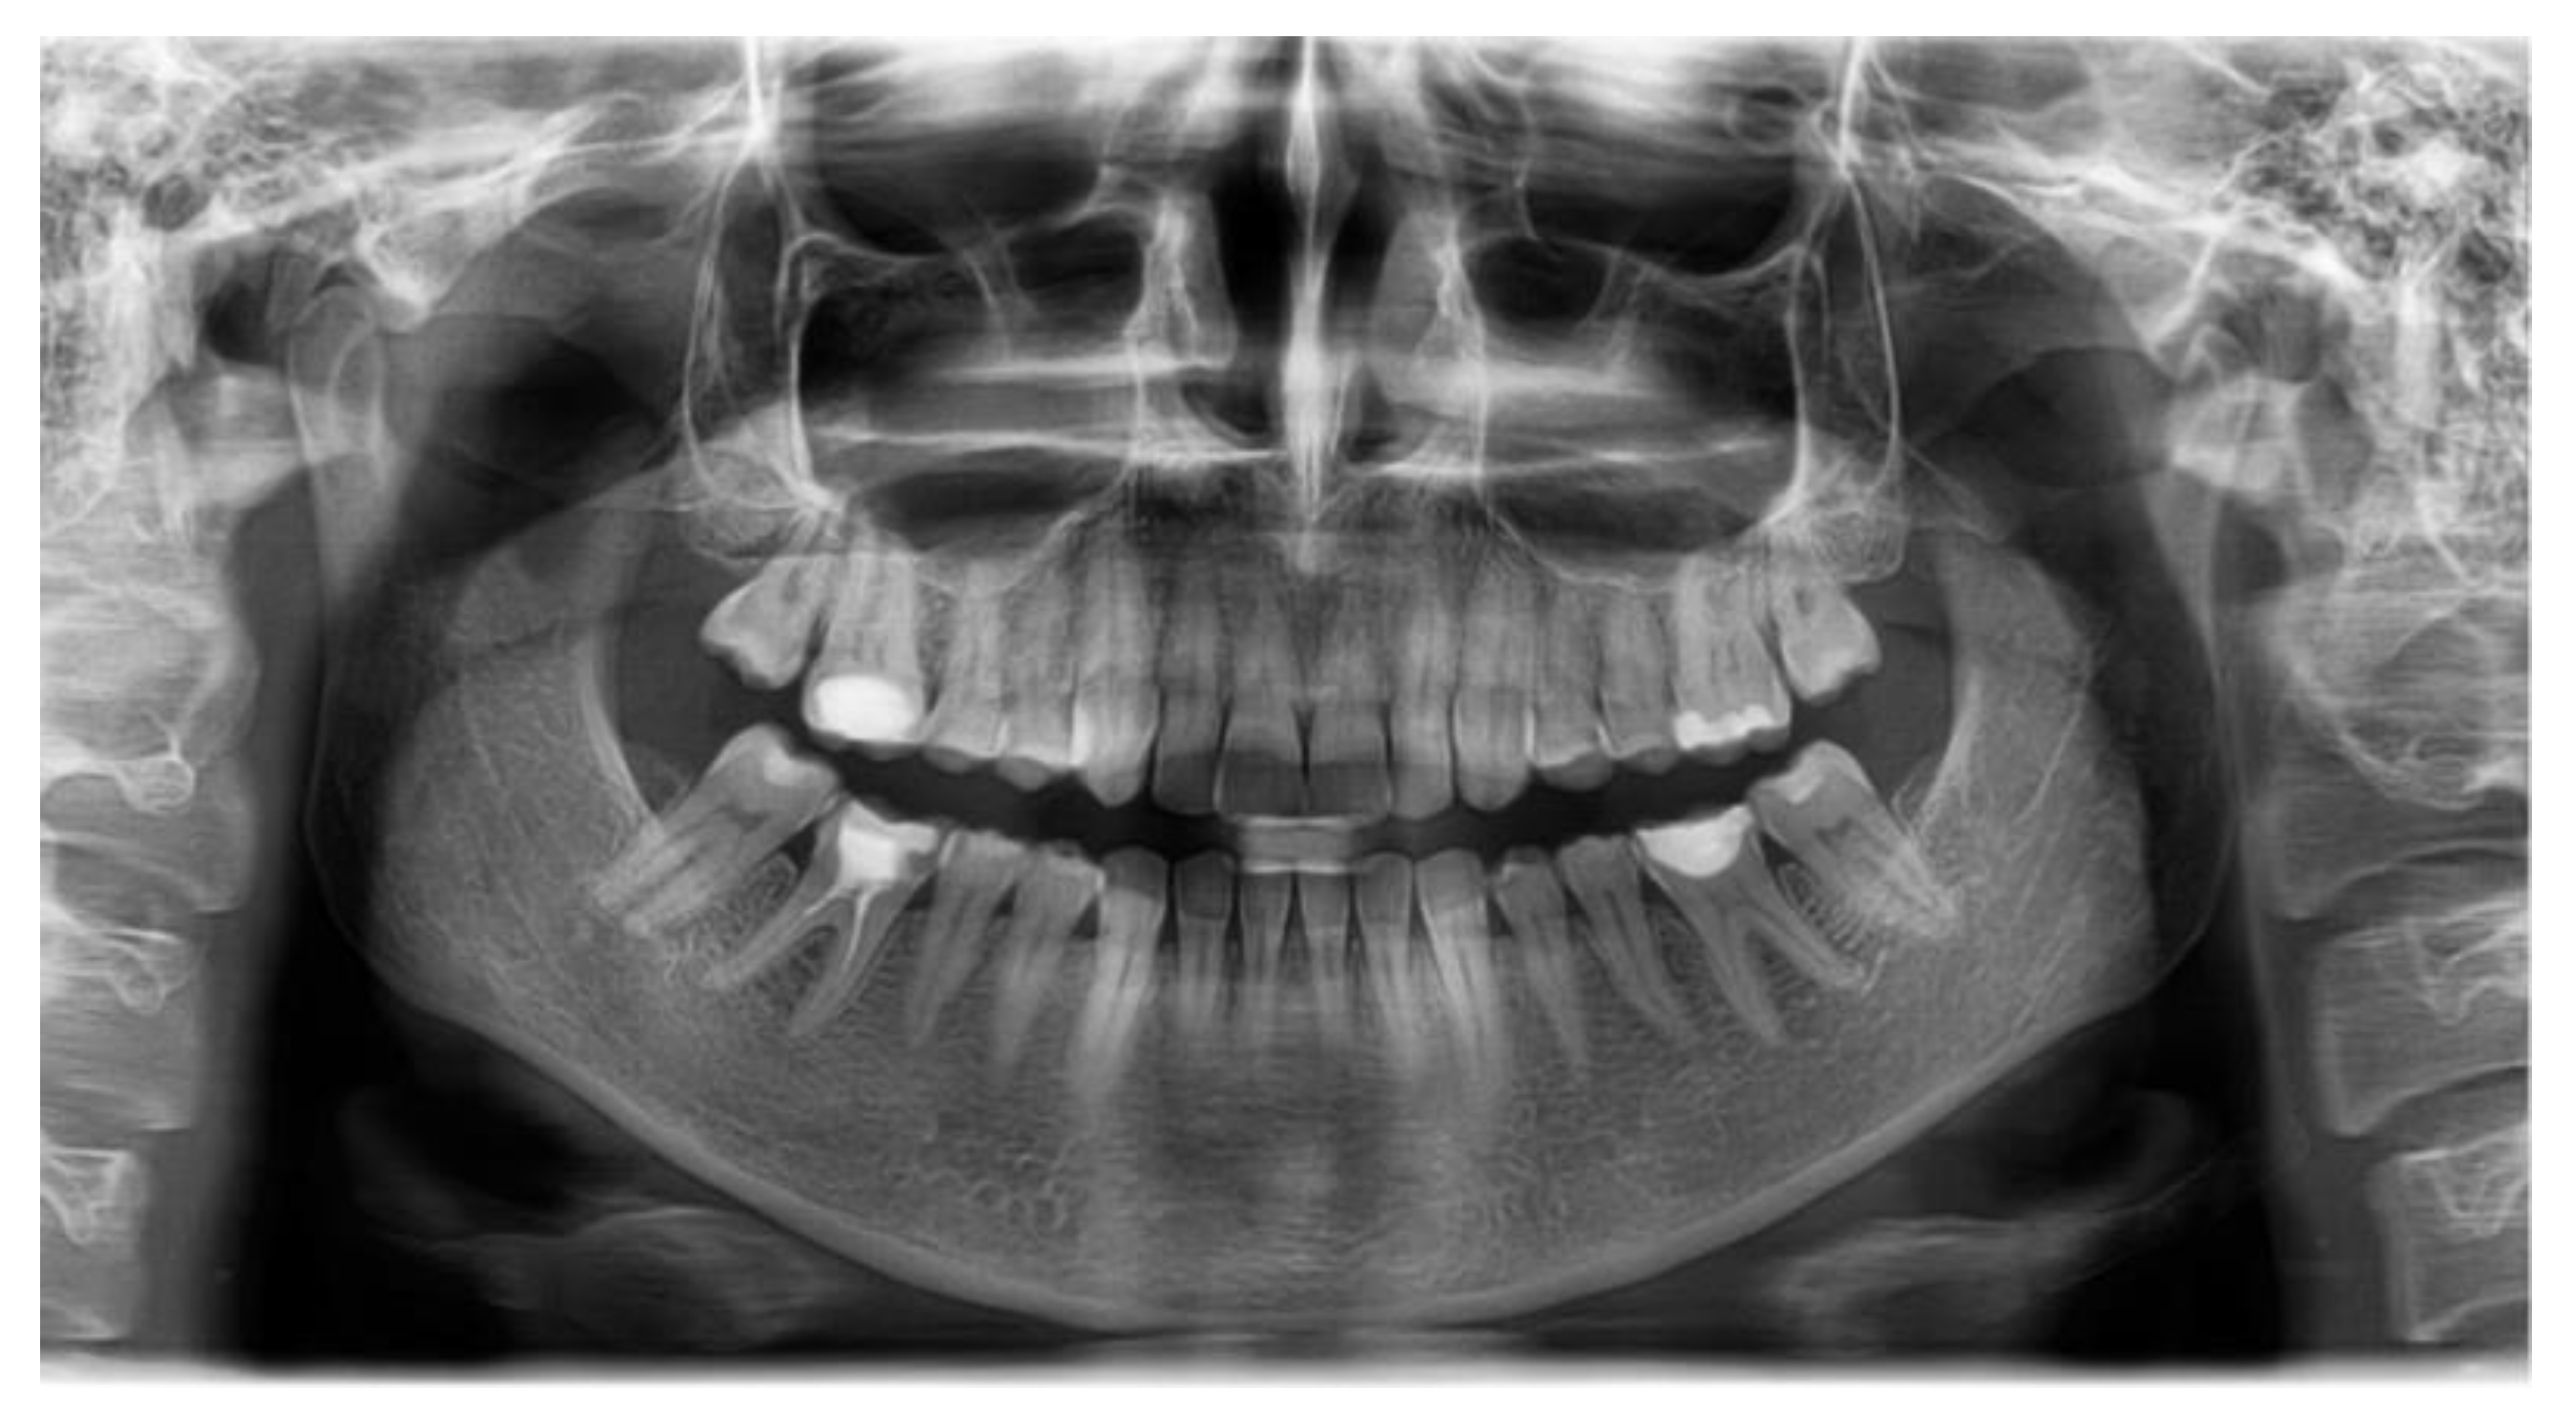

3.3. Case Report

| Magalhaes M.A. et al., 2016 [28] | Case report, 8-year-old male | Yes, ongoing | Squamous cell carcinoma, with positive staining for p16 in a patchy pattern suggestive of HPV | This rare case of squamous cell carcinoma was located in the gingiva and alveolar ridge, a common location for this demographic group; the post-operative evolution was without events, and the patient was considered disease free at 16 months after surgical resection. |

| SNA | 80.03 | 81.08 | 3.7 | Normal A-P position of the maxilla |

| SNB | 75.40 | 79.17 | 3.8 | Normal A-P position of the mandible |

| ANB | 2.46 | 4.63 | 1.8 | skeletal class II |

| FMA | 26.32 | 29.63 | 3.0 | Hypodivergent facial pattern |

| Gonial angle | 123.44 | 124.31 | 5.4 | Normal gonial angle |

| APDI | 74.22 | 85.74 | 4.0 | Skeletal class II |

| A to N-Perp (FH) | −2.58 | 0.4 | 2.3 | Retruded maxilla |

| B to N-Perp (FH) | −12.06 | −3.5 | 2.0 | Retruded mandible |

| Pog to N-Perp (FH) | −9.14 | −1.8 | 2.5 | Retruded chin point |

| FH to AB | 76.26 | 81 | 3.0 | Skeletal class II |

| A-B to mandibular plane | 77.41 | 69.3 | 2.5 | Large angle |

| Wits appraisal | 5.61 | −2.74 | 0.3 | Skeletal class II |

| Overjet | 4.79 | 2 | 2.0 | Large overjet |

| Overbite | 2.46 | 2 | 2.0 | Normal overbite |

| U1 to FH | 100.88 | 113.8 | 6.4 | Retroclined upper incisor |

| U1 to SN | 93.59 | 105.28 | 6.6 | Retroclined upper incisor |

| U1 to UOP | 70.28 | 55 | 4.0 | Retroclined upper incisor |

| IMPA | 80.50 | 91.62 | 3.2 | Retroclined lower incisor |

| L1 to LOP | 74.77 | 66 | 5.0 | Retroclined lower incisor |

| Interincisal angle | 152.29 | 128 | 5.3 | Uprighted interincisal angle |

| Cant of occlusal plane | 5.66 | 9.3 | 3.8 | Normal occlusal plane angle |

| U1 to NA(mm) | 0.10 | 4 | 3.0 | Retruded upper incisor |

| U1 to NA(deg) | 13.55 | 22 | 5.0 | Retroclined upper incisor |

| L1 to NB(mm) | 1.5 | 4 | 2.0 | Retruded lower incisor |

| L1 to NB(deg) | 9.52 | 25 | 5.0 | Retroclined lower incisor |

| Upper incisal display | 3.17 | 2.5 | 1.5 | Normal incisal display |

| Upper lip to E-plane | −3.42 | 0 | 2.0 | Retruded upper lip |

| Lower lip to E-plane | −2.22 | 0 | 2.0 | Retruded lower lip |

| Nasolabial angle | 114.84 | 95 | 5.0 | Retruded lip |

| Extraction Index | 159.69 | 153.8 | 7.8 | Normal |